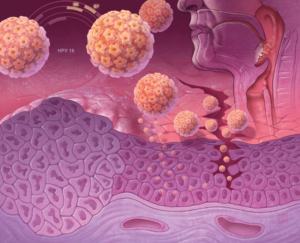

- Вирус папилломы человека (ВПЧ). Половые отношения с человеком с ВПЧ является наиболее распространенным способом инфицирования ВПЧ. Существуют различные виды ВПЧ, называемые штаммами.

- Снижение риска заражения ВПЧ путем вакцинации от ВПЧ или путем ограничения количества половых партнеров. Использование презерватива во время полового акта не может полностью защитить от ВПЧ.